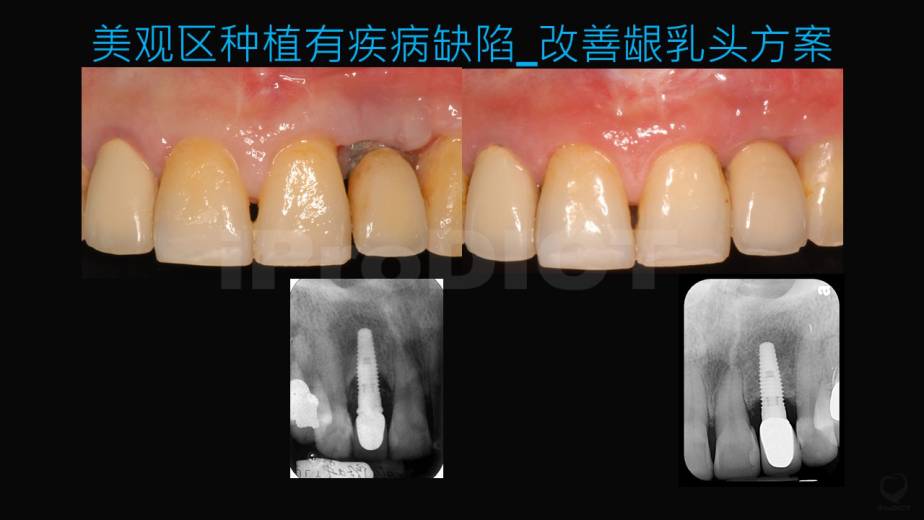

美观区BIC_有疾病缺陷之处置